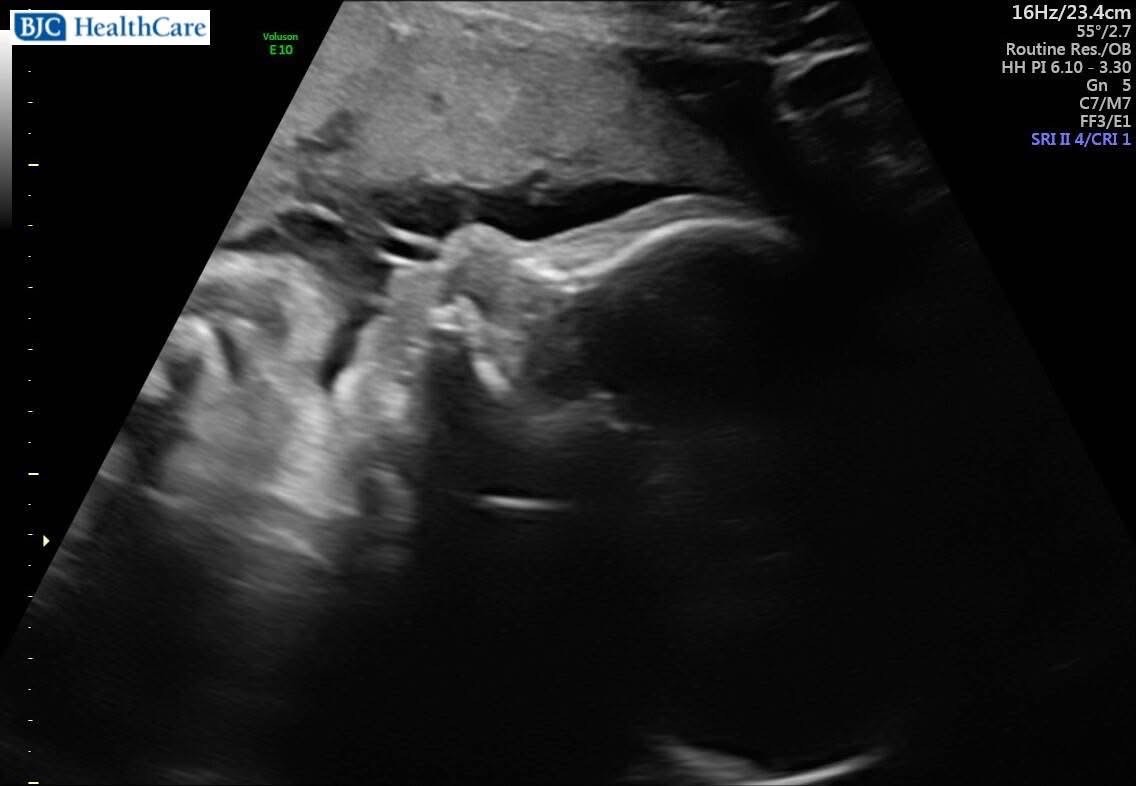

Hello everyone!! As you may know, our dear friend Emily is pregnant with baby boy Braxton Lee and due in December. Unfortunately at the 20 week mark, Emily and Austin found out that Mom's body does not make amniotic fluid and baby boy's kidneys have cysts. What does that mean? 1. Without fluid, Braxton cannot practice breathing while in Mommy's belly. and 2. With failed kidneys, dialysis will be required until he is big enough to undergo a kidney transplant. There is not much medical history on baby boy's condition, only failed trials called RAFT.

Currently, Emily is required to travel to Barnes in St. Louis a minimum of twice a week to inject fluid into the placenta since Braxton depletes it rather quickly while trying to grow, and it's necessary for him to learn to breathe.